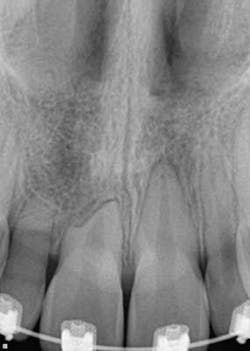

The retention of impacted canines can present with complications, namely resorption of the roots of adjacent teeth and cystic lesions of the follicle. (4)

When a full permanent dentition is present (with the exception of impacted canines), the labial/palatal position of the canine will have an influence on what the provider can do. (1) Arguably, obtaining a CBCT is considered mandatory and will allow for a more inclusive treatment plan creation. If angulation is favorable, then consideration to remove the primary canine and wait six months to see if there is movement of the permanent canine is an option. If extraction of the canine(s) is needed, then a premolar substitution, which is dependent on occlusion, can be used in the space. An implant can also be an appropriate alternative. When pulling a canine into the occlusal arch, there is risk involved. Trauma to adjacent teeth (root resorption) and ankylosis are some of the most common complications.The patient was put in full orthodontics and referred to a surgeon for extraction of the primary canines, exposure, and placement of retention on the impacted canines to pull them directly down from their current position.

A ballista appliance was used to prevent a facial pull of the canines in order to avoid and prevent resorption of the roots of the lateral incisors. As movement progressed over the course of the next year, eruption of the canines was considered a success. Once in position, they will be pulled facially into occlusion.